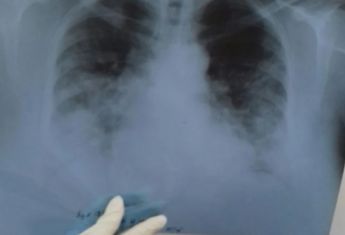

Специально для скептиков доктор опубликовала рентгеновские снимки своих пациентов, больных COVID-19.